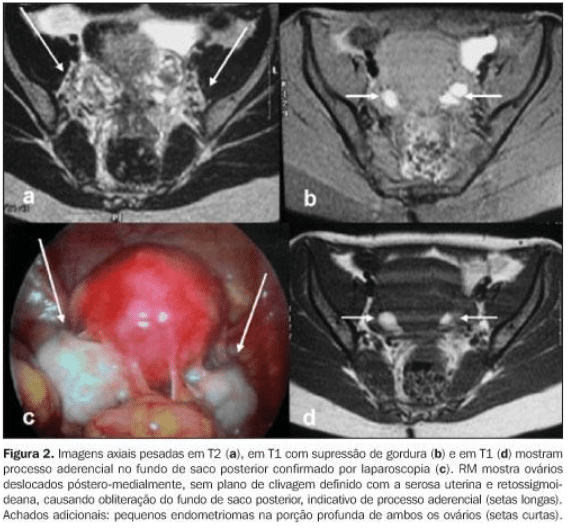

A supressão de gordura é útil porque muitas vezes as lesões de endometriose têm um sinal semelhante ao da gordura. Ela pode melhorar a visibilidade das lesões. Na imagem B da figura abaixo, é possível ver isso.